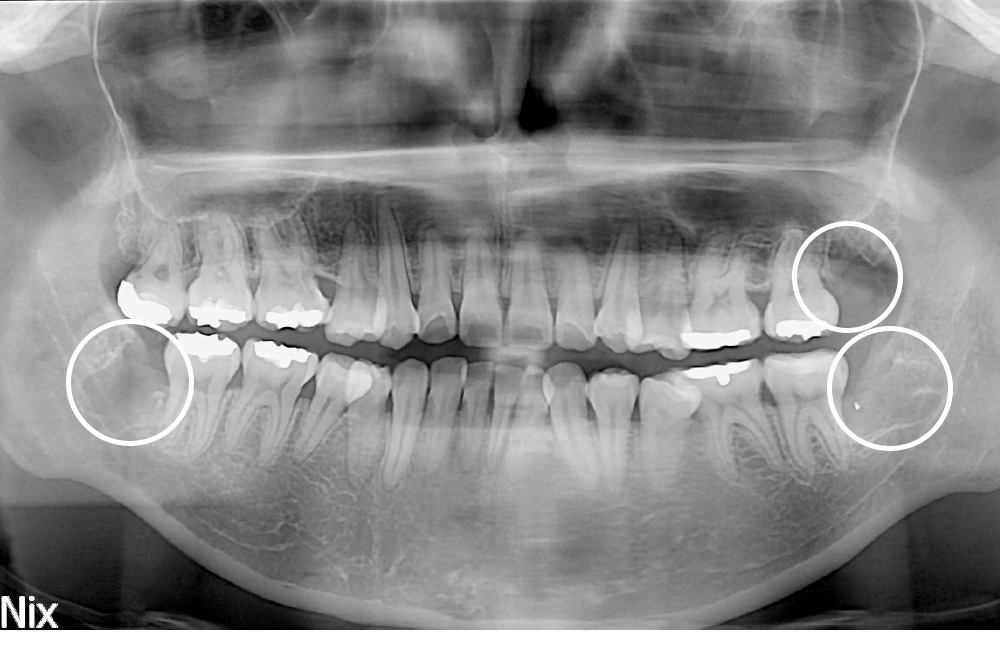

[사랑니] 매복 사랑니 발치

치료전 : 2018-04-16